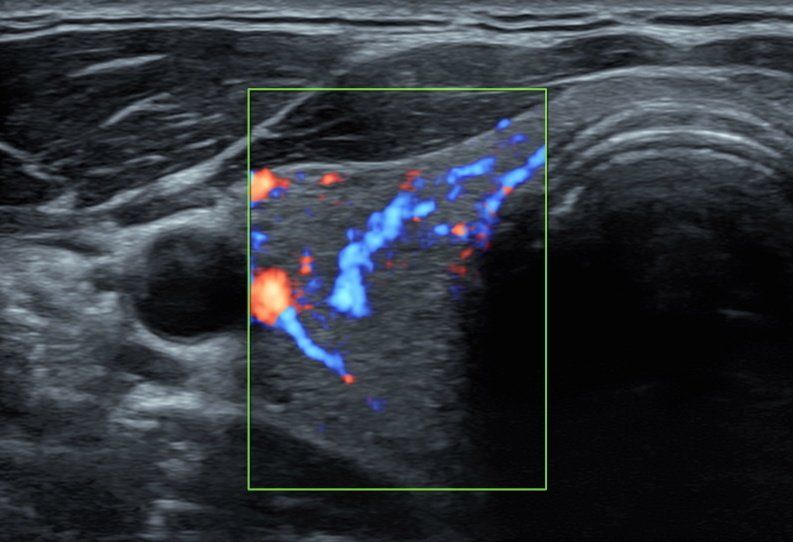

La diagnostica Eco-Color-Doppler si rende utile sia nello studio degli organi interni sia nella valutazione dei distretti vascolari arteriosi e venosi. Gli esami eco-color-Doppler sono indicati per lo studio delle carotidi/tronchi sovra-aortici (patologie cerebro-vascolari e cardiologiche), per la valutazione dell’aorta addominale (aneurismi, dissecazioni), per la valutazione delle arterie degli arti inferiori (arteriopatia ostruttiva, diabete), per la valutazione delle vene degli arti inferiori (insufficienza venosa, varici arti inferiori).